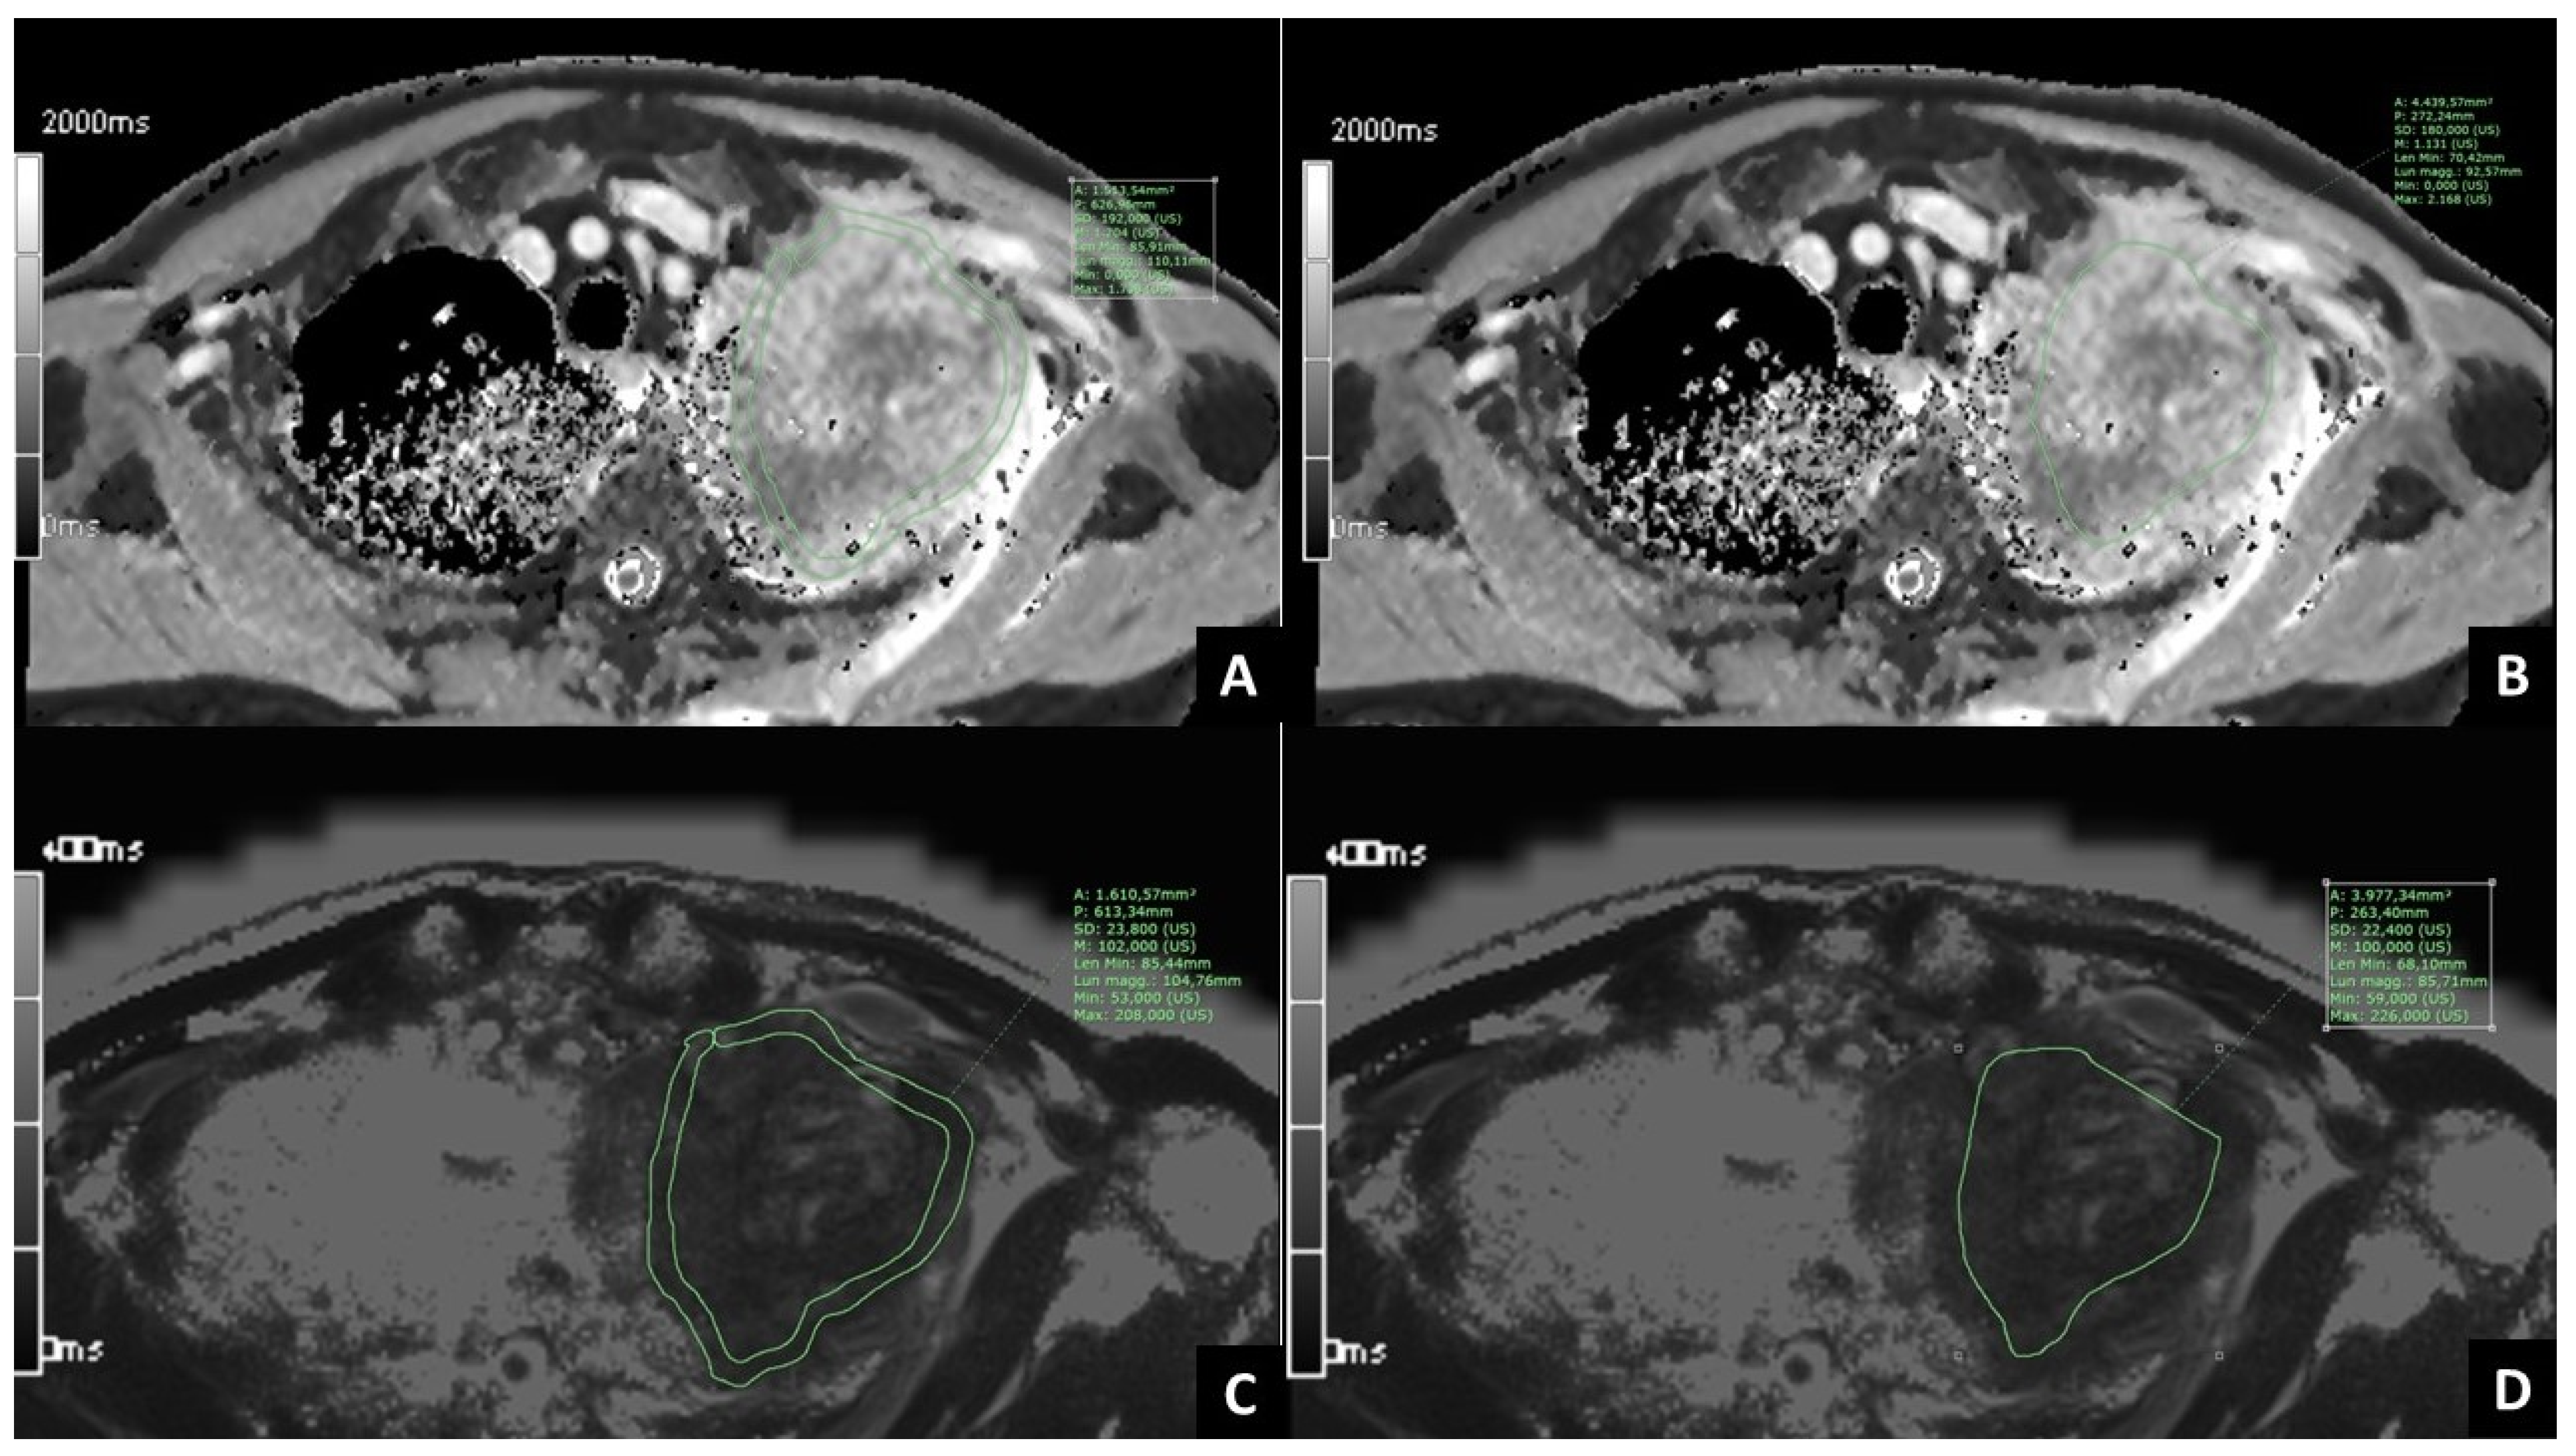

2.2. MRI Examination

2.3. Post-Processing of MRI Images